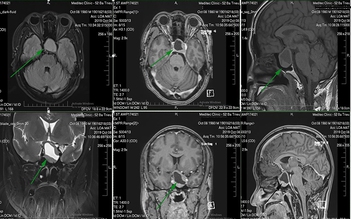

Uống 10 lít nước một ngày cũng không đã khát, không ngờ là do u não

4 dấu hiệu sớm của khối u não, người mắc nên đi khám ngay